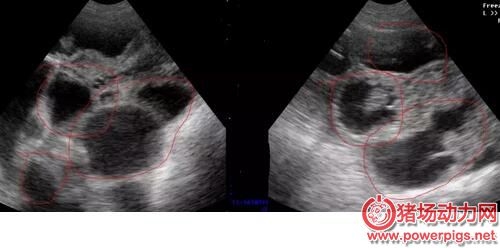

配完種之后要做的事情是什么? 肯定是檢查母豬是否妊娠啦..... 那么問題來了,到底什么時候檢查妊娠最為合適? 按理來說,早檢查可以盡快把沒有懷孕的母豬查找出來,而晚檢查可以盡可能把早期胚胎死亡的母豬也查找出來。 其實最好的策略是從輸精后第18天開始就用公豬來檢查母豬是否返情。隨后從第21天開始,第三周、第四周連續做兩次妊娠掃描診斷。 應該也有不少吃瓜群眾挺好奇不同階段的懷孕情況是怎樣的? 不同階段B超結果 第18-21天 在豬受孕18天后,B超已經可以檢測到胚泡,但是由于此時的胚泡形態較小,檢測時不容易被發現,需要操作員消耗大量時間來尋找。 母豬早期孕檢技巧: 1.母豬配種后18-21天; 2.測定時先找到膀胱暗區,小角度緩慢變換探頭探掃方向,在膀胱暗區前上方“亮帶”以上細致查找疑似的黑洞。 第21-35天 22-25天的胚胎很容易發現,此時將探頭放在檢測“三角區中”,只要位置正確立刻能發現孕囊,此時孕囊主要顯示為一個個的“黑洞”。 測孕小技巧 1.18-25天期間胎囊極速增長 2.早期胎囊為圓形或橢圓形,1-2天之后多數變為不規則 第25-35天 25-35天,孕囊會放慢變大的速度,逐步從“黑洞”內可看到一些白色的亮光出現,是胎兒的超聲反射,又稱為胎體反射。 測孕小技巧 1.25天以后可見胎體反射,此后胎體占了胎囊的大部分 2.32天時,能顯示胎兒骨骼鈣化的強回聲 第35-65天 35-65天,孕囊和胎兒會一起長大,會更容易發現“黑洞”中有亮斑,系胎兒的超聲反射,也稱胎體反射,此時的圖形孕囊和胎體反射會比25-35天期間更大,更明顯。“黑洞”面積減少,是因為羊水減少。 測孕小技巧 1.35天時,呈現胎兒骨骼鈣化的強烈回聲,羊水面積減少 2.45天時,胎兒體腔分化 第65-100天 65-110天,胎兒已經長大,羊水減少。80天,胎兒的肋骨可清晰見到,從不同角度可呈現“虛線橢圓”亮斑,或者“弧形”亮斑。 測孕小技巧 1.80天時,胎兒脊柱清晰顯示 2.95天時,胎兒脊椎、胸骨及體腔分辨清晰 不過也有些小伙伴反映,母豬經常返情,到底是什么原因呢?妊娠成功又需要些什么條件呢? 發情周期約21天。在授精后18-24天發情的母豬(沒有懷孕)稱為規律性返情母豬。以此類推,在42天或者63天左右返情的母豬也稱為規律性返情母豬,返情高峰期分布在這些天。分散在其他天數的稱為非規律性返情母豬。 返情 返情/復配的原因 最常見的原因——授精管理差;催情不足;發情不充分/太短;授精時間選擇好;3周后返情;發情檢查不足;授精時間選擇不好;“發情周期”小于18天;3周和/或6周后返情 配種員:態度,工作壓力 管理系統:催情/發情檢查、輸精管理、數據記錄 營養:喂料量和飼養管理 欄舍:飼養密度、環境、光照、溫度、占用率 母豬:出生缺陷,發育狀況 繁殖與傳染病 種豬場,疾病很少成為繁殖問題的一個重要因素,傳染病通過以下兩套途徑殺死胚胎: 傳染病病毒損壞了胚胎、胎膜或者子宮,引起胚胎死于子宮中(如細小病毒、藍耳病毒); 發燒引起前列腺素的大量釋放,前列腺素會引起流產(如豬丹毒、流感、腸道病毒、經典豬瘟、肺或腸道傳染病引起的發燒)。因此在發燒期間要用退燒藥。如果多個母豬幾乎同時流產的話,要考慮傳染病可能是問題的源頭。 寄生蟲:由疥螨、豬虱或者皮膚狀況不好引起的皮炎會使母豬焦躁不安。這種焦躁不安也是造成母豬返情的一個原因。 如果懷疑是疾病問題(不吃料、精神萎靡、皮膚發白、糞便),一定要測量母豬的體溫。涂點潤滑劑或者唾液,將溫度計插入母豬肛門內至少5cm。讓溫度計的頂端緊貼著腸壁,糞便或者腸道內的空氣都會影響測定結果。健康妊娠母豬的體溫是38-39°C,超過39.5°C就是發燒了。 氣溫 熱應激會導致母豬流產、返情。 夏天,不要在一天中最熱的時候喂豬;在豬舍向陽面,用塑料薄膜、石灰或者乳化漆遮蔽窗戶;提供平和、安靜的環境;高溫時不搞預防接種;每天檢查配種舍、待配舍和妊娠舍的溫度。 9月中旬到10月底,會出現秋季繁殖力下降現象:后備母豬發情開始變慢,非規律性返情和規律性返情或流產越來越多。 秋天晝夜溫差最大,為預防秋季繁殖力下降,從7月底開始將光照時間增加到每天16個小時,同時要確保配種舍和待配舍晚上的溫度不要太低(<18°C),提前做好通風管理,避免出現賊風。提高斷奶后的和配種后的母豬的飼喂量。因為低溫條件下,更多的能量用于維持需要,從而使得用于繁殖的能量減少。 分析 少于18天的發情期從生理學角度上講是不可能的。 3周左右的規律性返情的責任在于配種員,此外妊娠早期會有胚胎死亡。對于36-48天或者56-68天出現的返情,3周時出現的返情被錯過的可能性極大。 25-36天非規律性返情的原因常常是胚胎死亡。在此期間未被發現的母豬過21天會再返情,即在49-56天返情。 妊娠成功的因素有哪些 配種員:催情、發情檢查、輸精時間、輸精技術 公豬:精液質量、精液儲存、精液貨架壽命、公豬差 母豬/胚胎:母豬體況不好、應激、疾病、光照(強度和時間) 再者,又有大伙們表示母豬流產也不少見,求解求解? 胚胎死亡發生的階段 排卵:卵子少或質量低(營養不良); 受精:授精不佳,原因:配種員或公豬; 胚胎死亡:胚胎可能死于各種原因,如疼痛或瘸、轉運應激、喂料站工作不正常、疥螨、為爭奪統治地位而打斗、環境不良、能量負平衡; 胎兒死亡(妊娠35天以后):子宮內空間不足(胎兒太多)或者死于發燒/疾病(不常見)。 胚胎存活的關鍵 在妊娠35天之前保持平和、安靜是必不可少的,因為此前胚胎對子宮內環境變化還非常敏感。從妊娠后第12天到第18天,胚胎發出雌激素信號,所以黃體完整保留,妊娠繼續。骨骼的形成于妊娠后第30天。 來源:溫氏養豬公開課 |